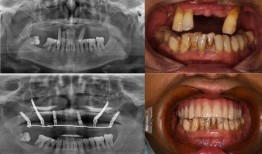

佛山种牙爆料事件视频曝光,揭露行业乱象引发关注

最近佛山那边的种牙事件可是闹得沸沸扬扬的,咱们得好好来聊聊这个话题。你有没有看过那个爆料视频?简直让人瞠目结舌啊!事件回顾:佛山...